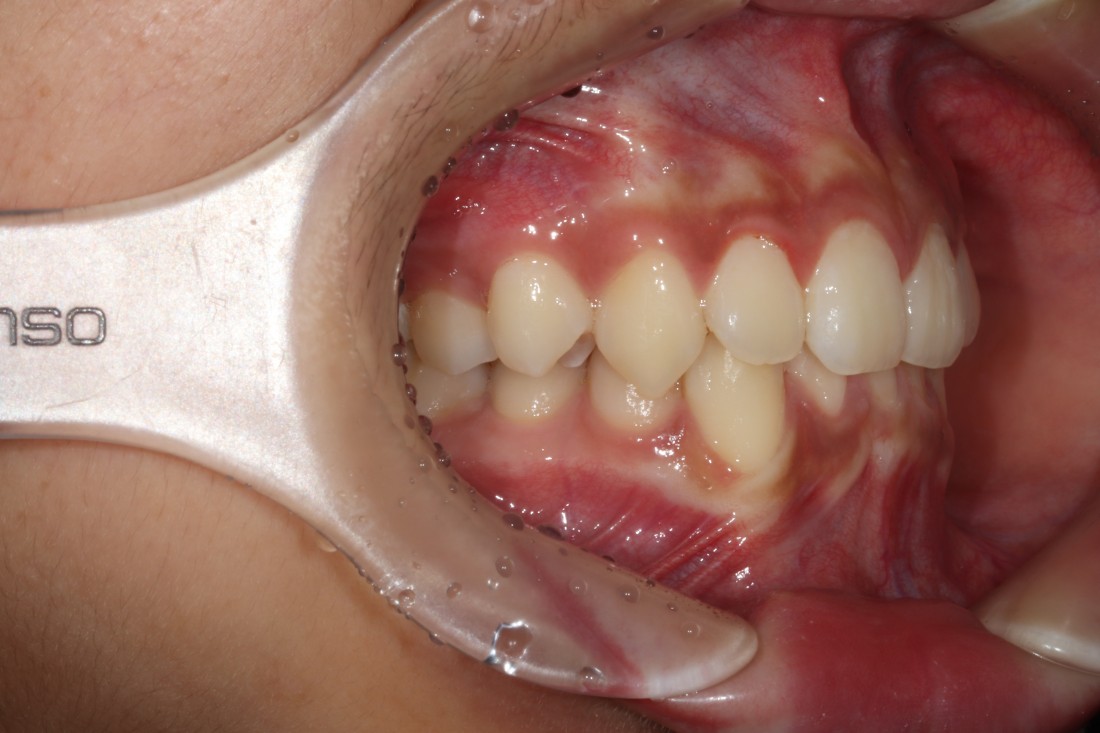

다양한 과개교합 교정 전/후 사진은

위의 사진을 클릭하시면 확인하실 수 있으며,

부정교합은 단순히 치열을 고르게 하는

치열교정과는 다르게

턱관절 건강도 따져보아야하고,

충치치료 등 필요한 진료들이

다양하게 있을 수 있기 때문입니다.